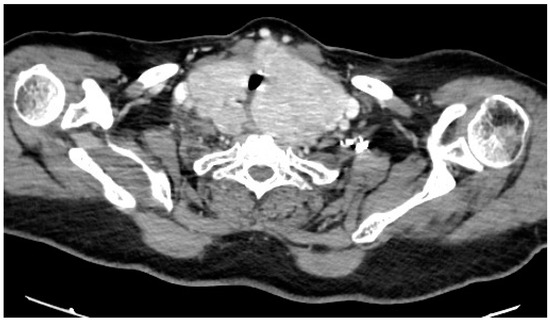

体格检查显示患者身高149厘米,体重84公斤,BMI为37.8 kg/m2(归类为肥胖:BMI ≥ 30)。她的颈周测量为49厘米,位于颈椎中部与前颈部之间。上呼吸道检查显示Mallampati评分为4,临床上明显有大型甲状腺肿,未观察到颅面异常。检查时甲状腺下缘无法触及。然而,颈部和胸腔的计算机断层扫描(CT)确认甲状腺多节增大,伴有咽后部扩张、胸骨下肿大和气管压迫,且无显著脱位。呼吸障碍监测显示严重阻塞性呼吸暂停(OSA),AHI为每小时32次事件(归类为严重OSA:AHI≥30),主要表现为阻塞性低通气。

术前呼吸管理后,患者接受了新的耳鼻喉科上呼吸道内镜检查,显示擧绳类压迫伴有水肿,且两声带活动正常。随后,在突尼斯拉拉布塔大学医院耳鼻喉科进行了全身麻醉下的全甲状腺切除术。术后,患者报告了声音质量的轻微变化。对切除甲状腺的宏观检查显示尺寸增大,右叶7×5 × 3厘米,左叶12 × 7 × 5厘米,地峡3×2厘米。组织学分析确认无恶性肿瘤。患者接受了左甲状腺素替代疗法,剂量为125微克/天。